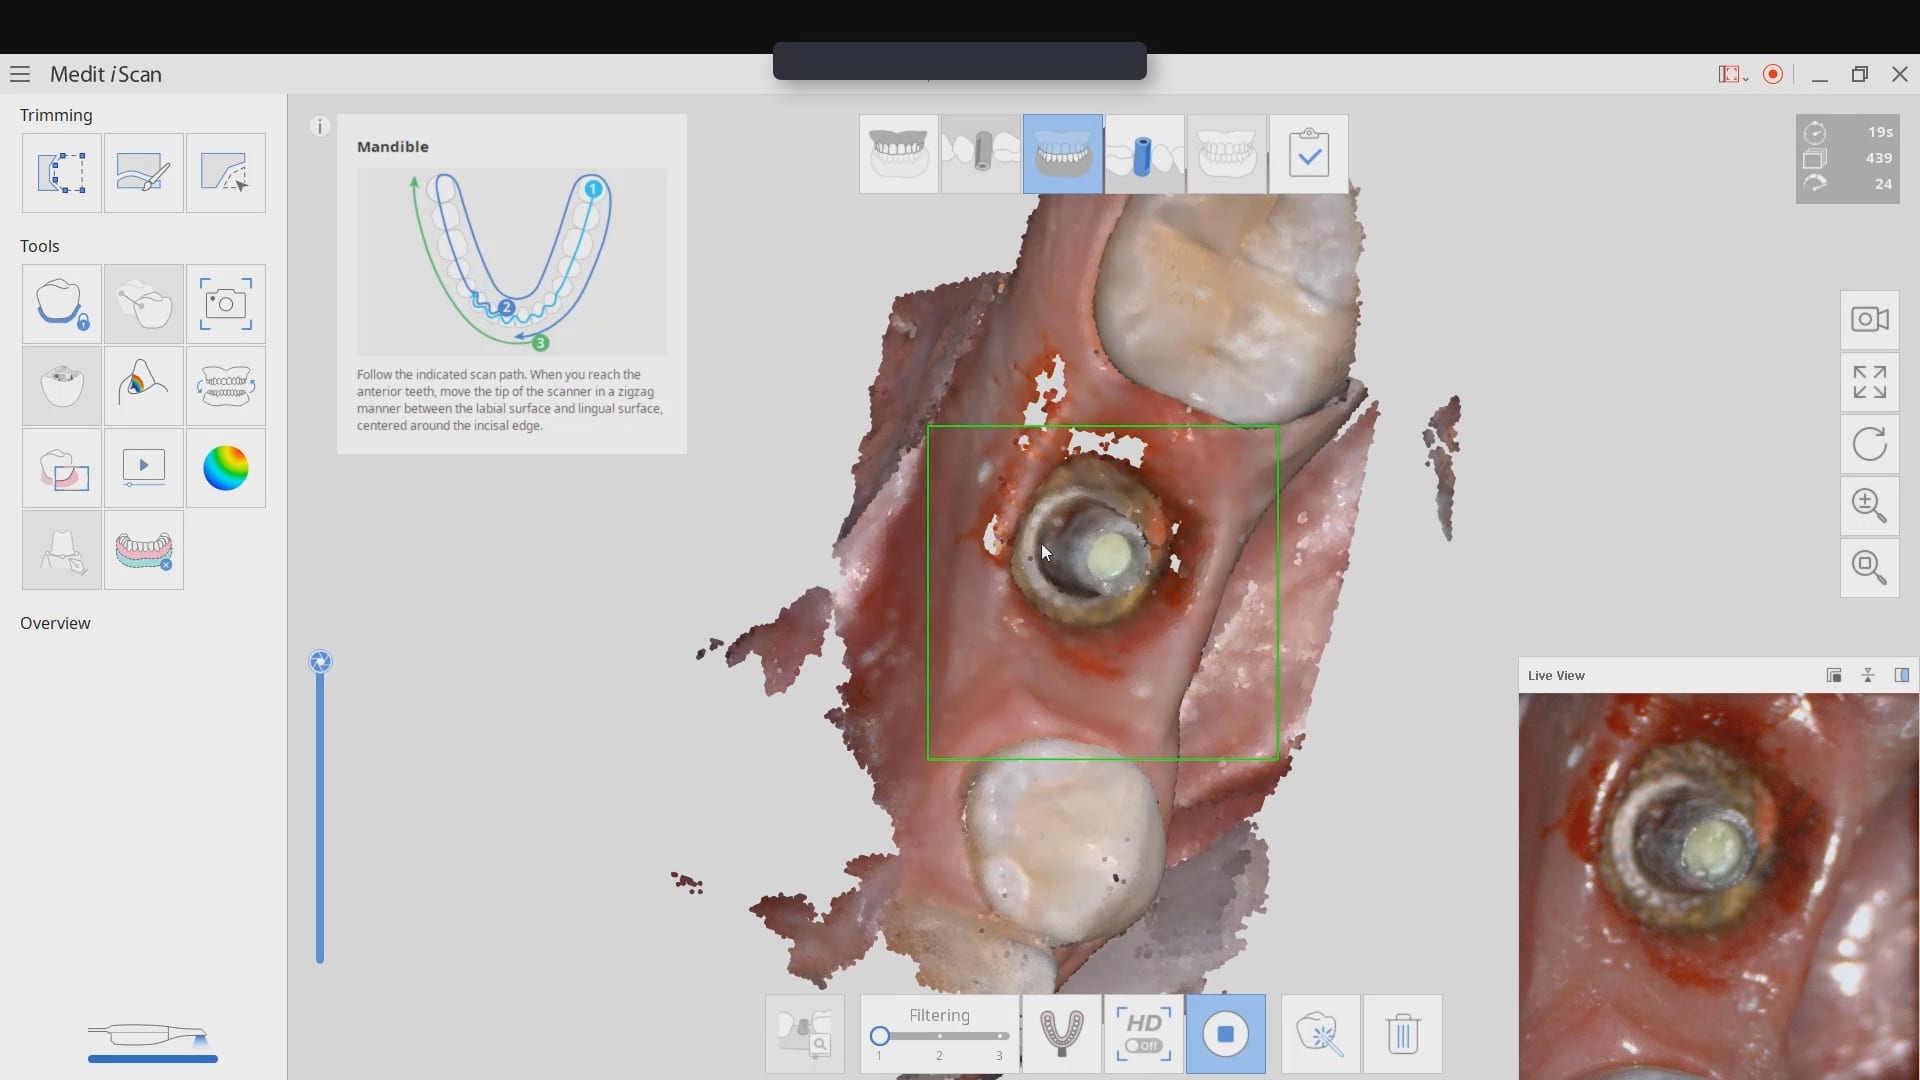

Medit has launched a software that is the greatest advancements in digital dentistry in more than a decade! With artificial intelligence, you can identify the scanbody during intra-oral digital scans. […]

In this article we demonstrate how two separate implants are placed with guided surgery and then scanbodies are used immediately after placement to capture the location of the fixtures. While […]